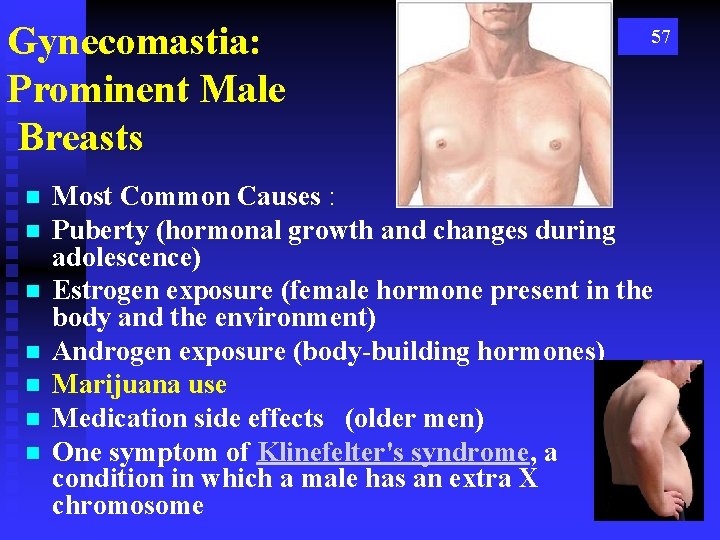

Gynecomastia: Prominent Male Breasts n n n n 57 Most Common Causes : Puberty (hormonal growth and changes during adolescence) Estrogen exposure (female hormone present in the body and the environment) Androgen exposure (body-building hormones) Marijuana use Medication side effects (older men) One symptom of Klinefelter's syndrome, a condition in which a male has an extra X chromosome